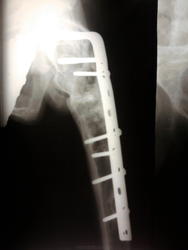

Двухсторонние литические очаги, с четкими, местами склерозироваными контурами. Старый консолидированый перелом левой бедренной кости, после металлоостеосинтеза металлической пластиной. Миеломная или мтс проявили бы себя более агрессивной деструкцией.

tatyana, Вам "зачет"! Здесь действительнро болезнь Реклингхаузена. Наблюдаю данного пациента лет 7. За это время его патологический перелом левой бедренной кости так и не срастается, приобретая все более атрофичный вид в виде перетяжки на уровне излома, потому и держат с металлом до сих пор. Классическая "пастушья палка". Справа в теле подвздошной кости и (менее выраженно) ближе к задней нижней ости, а также в большом вертеле также имеются литические очаги, относительно стабильные за время наблюдения.

"самоуверенность дилетантов - предмет зависти профессионалов"